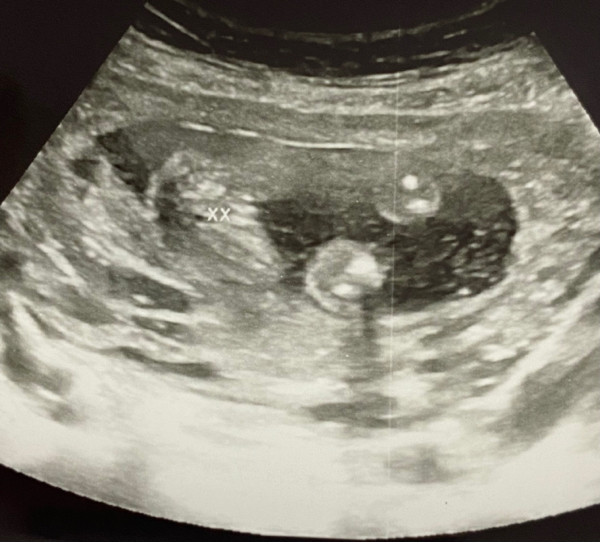

بدور مبرووووك بنوته نفس الي صار معى الي يجى من الله حياه الله اهم شى يكنون بصحه

بدوور مبروك البنووووته واحلى جحفله